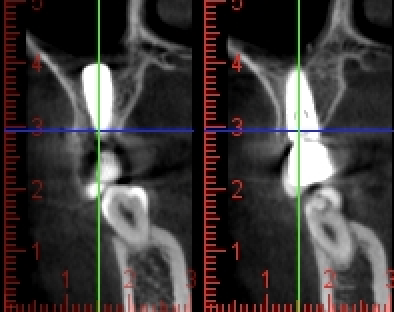

写真は同一部位のレントゲン写真とCT画像です。レントゲン写真は顎骨の形態や走行する神経の位置、歯が生えている方向把握することはできても2次元的な位置関係でしか把握できません。つまり歯や神経の位置がわかっていても実際にどのくらいの位置関係にあるのかを正確に判断することはレントゲン写真では不可能なわけです。しかし、歯科用CT画像では顎骨の形態や走行する神経の位置、歯の生えている方向、さらには骨密度の状態を3次元的に画像化する事が可能なため、より正確な診断する事ができます。